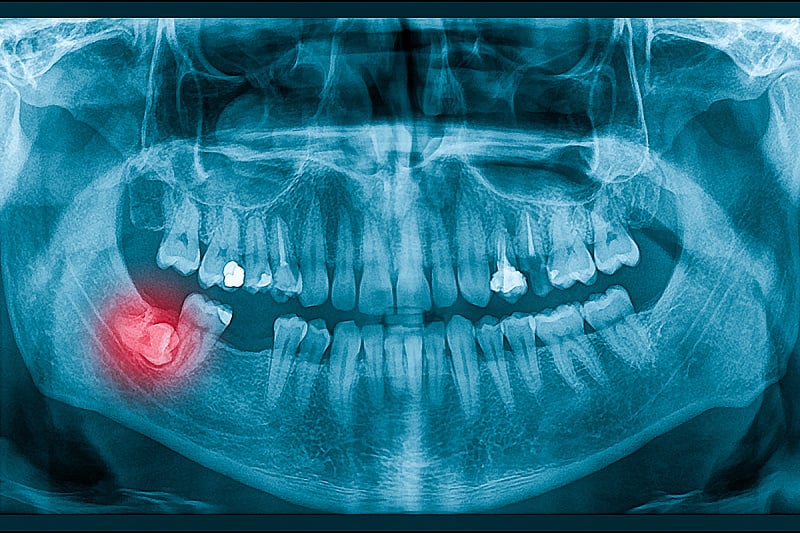

Cilj lijeka je pomoći osobama koje pate od gubitka zuba, stanja za koje nema trajnog lijeka.

Istraživanje se fokusira na gen-1 povezan s preosjetljivošću maternice (USAG-1), protutijelo za koje se zna da inhibira razvoj zuba kod sisavaca. Godine 2021. godine naučnici s Univerziteta Kyoto, koji su također uključeni u trenutna ispitivanja, identificirali su monoklonsko protutijelo sposobno poremetiti interakciju USAG-1 s koštanim morfogenetskim proteinima (BMP), koji igraju ključnu ulogu u formiranju zuba.

Ako bude uspješna, bolnica Kitano planira proširiti liječenje na djecu u dobi od 2 do 7 godina kojima nedostaju najmanje četiri zuba, s krajnjim ciljem da lijek bude široko dostupan do 2030. Dok je trenutni fokus na pacijentima s urođenim nedostatkom zuba, Takahashi se nada da bi tretman mogao pomoći svima koji su izgubili zub.